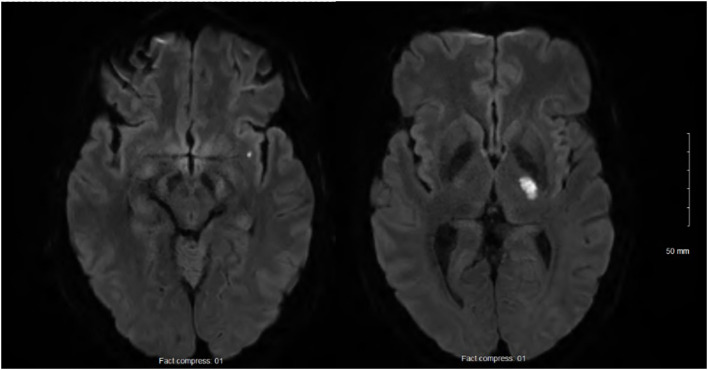

甲羟戊酸激酶缺乏症(MKD)是一种遗传性自身炎症综合征,由双等位基因甲羟戊酸激酶(MVK)突变导致类异戊二烯生物合成受损。这种代谢缺陷导致先天免疫失调,特别是白细胞介素-1β释放过多。虽然通常在儿童时期表现为周期性发烧,但越来越多的证据将MKD与异质成人表型与免疫介导的终末器官损伤联系起来。我们报告一个成年男性的腿部疼痛和手指发绀,随后急性缺血性中风,黄斑皮疹,和淋巴结病。他表现出固有免疫激活的经典标记,包括c反应蛋白的持续升高。基因检测发现已知的MVK致病变异C . 1129g >A (V377I)和一种新的错义变异C . 1049a >C (Q350P)具有复合杂合性。Q350P的结构建模显示GHMP激酶结构域的破坏,预测会破坏甲羟戊酸激酶构象并损害其功能。淋巴细胞甲羟戊酸激酶活性为55%(正常为60%)。用canakinumab阻断白细胞介素-1β开始,炎症的血液标记物正常化,进一步支持先天免疫失调的核心作用。该病例突出了一种新的MVK错义变体(Q350P),其甲戊酸激酶活性低于正常水平。患者的复合杂合状态和部分保留的甲戊酸激酶活性可能解释了减弱的全身特征和延迟的临床发作。值得注意的是,缺血性中风是最初表现的一部分,这表明甲羟戊酸激酶缺乏主要表现为成年期的血栓炎性并发症,即使在没有反复发热发作的情况下。这扩大了MKD的表型谱,并强调了在与全身性炎症标志物的隐源性缺血性卒中的鉴别诊断中考虑成人发病的自身炎症综合征的必要性。它还支持细胞因子靶向治疗在这种情况下的效用。

Mevalonate kinase deficiency (MKD) is an inherited autoinflammatory syndrome resulting from impaired isoprenoid biosynthesis due to biallelic mevalonate kinase (MVK) mutations. This metabolic defect leads to dysregulated innate immunity, particularly excessive interleukin-1β release. While typically presenting in childhood with periodic fevers, expanding evidence links MKD to heterogeneous adult phenotypes with immune-mediated end-organ damage. We report an adult male presenting with leg pain and finger cyanosis followed by acute ischemic stroke, macular rash, and lymphadenopathies. He exhibited classical markers of innate immune activation, including persistent elevation of C-reactive protein. Genetic testing identified compound heterozygosity for the known MVK pathogenic variant c.1129G>A (V377I) and a novel missense variant, c.1049A>C (Q350P). Structural modeling of Q350P revealed disruption of the GHMP kinase domain, predicted to destabilize mevalonate kinase conformation and impair its function. The measurement of mevalonate kinase activity in lymphocytes was at 55% (normal >60%). Interleukin-1β blockade with canakinumab was initiated, and the blood markers of inflammation normalized, further supporting a central role for innate immune dysregulation. This case highlights a novel MVK missense variant (Q350P) with subnormal mevalonate kinase activity. The patient's compound heterozygous state with partially preserved mevalonate kinase activity may explain the attenuated systemic features and the delayed clinical onset. Remarkably, ischemic stroke was part of the initial presentation, suggesting that mevalonate kinase deficiency can manifest primarily through thrombo-inflammatory complications in adulthood, even in the absence of recurrent febrile episodes. This expands the phenotypic spectrum of MKD and underscores the need to consider adult-onset autoinflammatory syndromes in the differential diagnosis of cryptogenic ischemic strokes with markers of systemic inflammation. It also supports the utility of cytokine-targeted therapies in such contexts.